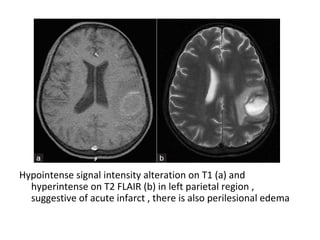

Hypointense signal intensity alteration on T1 (a) and

hyperintense on T2 FLAIR (b) in left parietal region ,

suggestive of acute infarct , there is also perilesional edema